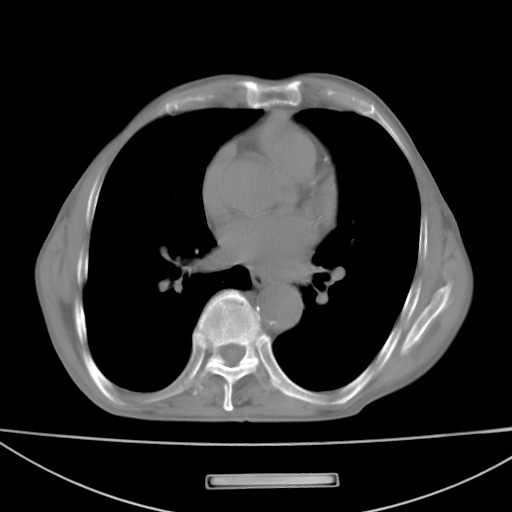

标题: CT13796:请会诊右上费病变!

患者男80岁,反复咳嗽多年,咳喘伴咯血1月

右上肺周围型肺癌伴肺门淋巴结转移.右上肺继发型肺结核.

右上肺周围型肺癌伴肺门淋巴结转移

右肺上叶占位性病变,考虑周围型肺癌,肺门淋巴结转移。要是能提供更多的临床资料就好了,以供鉴别诊断。

右肺尖周围型肺癌伴肺门淋巴结肿大

右肺尖结核

右肺上叶占位性病变,考虑周围型肺癌,肺门淋巴结转移。

右上肺周围型肺癌伴肺门、纵膈淋巴结转移

考虑为:右肺上叶肺癌伴阻塞性肺炎、右肺门及纵膈淋巴结转移。